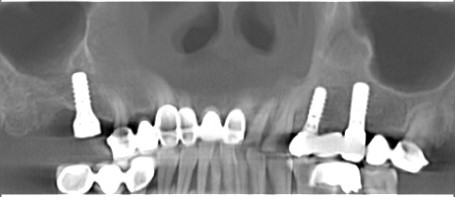

在数字化种植导板下,通过CBCT、口扫等途径获取口腔三维信息内容。使患者在种植之前就可以了解到种植方案的相关细节,清晰地看到牙齿修复之后的模拟展示图,提前预知种植术后的效果。

二、精准控制 更安全

在数字化种植导板下的外科手术更加精准。种植体植入方向、位置、角度、深度等一目了然,即可将种植体精准植入到最佳位置,获得更优异的临床效果,手术安全性更高。